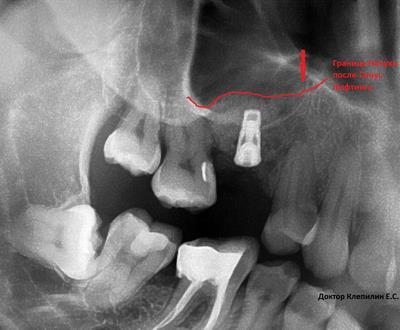

Что такое синус-лифтинг и зачем его проводят? Синус-лифтинг это вспомогательная операция при установке имплантатов. Для установки имплантатов нужны хорошие условия и в первую очередь это объем костной ткани в которую устанавливается имплантат. А объема не всегда достаточно. На верхней челюсти, в области жевательных зубов хирурга ограничивает гайморова пазуха. Когда расстояние до пазухи совсем мало, всего несколько миллиметров, применяют методику синус-лифтинга. Дно гайморовой пазухи приподнимают, проводят костную пластику и устанавливают имплантат. Операция требует высокой квалификации хирурга-стоматолога, надежных материалов и качественного инструментария.